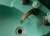

Прямое флуоресцентное окрашивание антителами, показывающее амебный менингоэнцефалит, вызванный Naegleria fowleri. Изображение: CDC